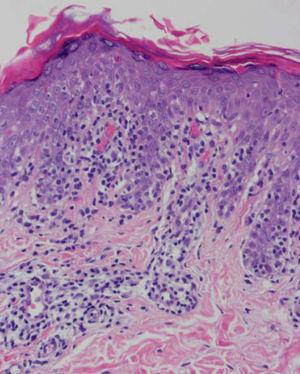

Se practicaron varias biopsias cutáneas, algunas de ellas sin alteraciones significativas. En otras se observó (figs. 4-6) una epidermis con hiperqueratosis y paraqueratosis focal, elongación de las crestas interpapilares y focos de degeneración hidrópica basal, con algún cuerpo apoptótico aislado. En dermis superficial y media existía un infiltrado linfocitario perivascular. Llamaba la atención la exocitosis de linfocitos atípicos intraepidérmicos, alguno de ellos con halo claro perinuclear y en alguna zona incluso iniciando la formación de microabscesos de Pautrier.

Fig. 4.—Paraqueratosis focal, elongación de crestas interpapilares, focos de degeneración hidrópica basal. (Hematoxilina-eosina, ×40.)

Como ocurrió con nuestro paciente, el estudio histopatológico en los estadios iniciales de la enfermedad puede ser muy inespecífico, lo que motiva además el retraso diagnóstico. En las fases más avanzadas revela la presencia de epidermotropismo de linfocitos anómalos, que a veces constituyen microabscesos de 5,6,8,11-23. En contraste con la micosis fungoide clásica, en esta variante parece que se observa un epidermotropismo más llamativo en contraste con un infiltrado linfocitario moderado en la dermis24.